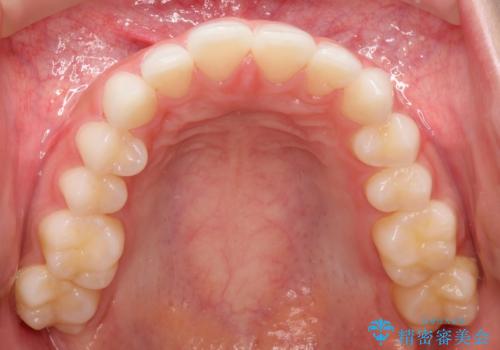

出っ歯の矯正治療 歯を抜かずにインビザラインで

- インビザラインで出っ歯を治したいとの希望がありました。

上顎の歯を全体的に後方に移動させて前歯を引っ込める計画としました。

インビザラインで目立たずに、痛みも少なく矯正治療を終えることができ満足していただけました。